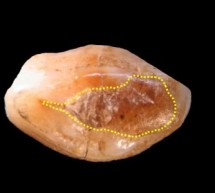

Nga Lorena Stroka Me sa duket mbushjen më të vjetër në botë kanë arritur të zbulojnë një ekip shkencëtarësh. Hulumtuesit e Qendrës Ndërkombëtare për Teori Fiziktë të Italisë analizuan dhëmbin e gjetur të një burri në një shpellë pranë Triestës, para 100 vjetësh, mirëpo, atëherë, kjo gjetje kaloi pa u vënë re. Shkencëtarët nuk janë plotësisht të sigurtë nëse mbushja u bë para vdekjes së burrit (bëhet fjalë p ...